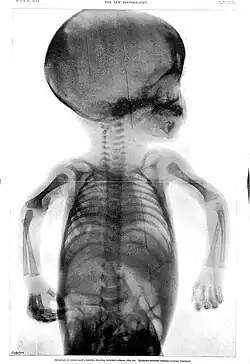

Rowland's career began in medical journalism while he was still a medical student when, in 1896, as Hart's intern, the year following the discovery of X-rays,[6] the BMJ appointed Rowland as "Special Commissioner" to produce a report on the clinical use of X-rays titled "Report on the Application of the New Photography in Medicine and Surgery."[3][6][a] It was published in 17 parts between 8 February 1896 and 12 June 1897.[3] In May 1896, he founded the world's first X-ray journal, the Archives of Clinical Skiagraph, a radiology journal that preceded the British Journal of Radiology.[3][6] In the preface to the first issue, written in April 1896, he wrote that "the object of this publication is to put on record in permanent form some sort of the most striking applications of the new photography to the needs of medicine and surgery".[6] He coined the term "skiagraphy" to describe the making of X-ray pictures and wrote some of the early works on radiology.[3] Without any radiology experts or X-ray departments at the time, his journal became an essential reading.[6]